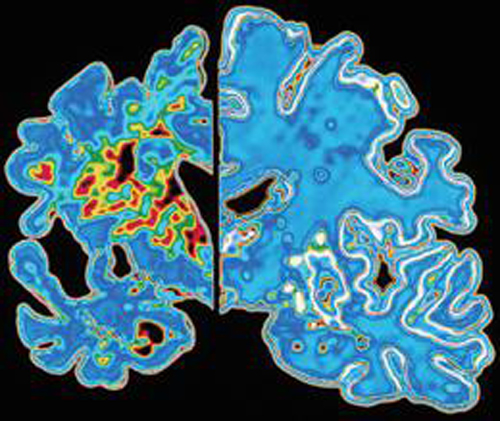

Oltre alla gene mutato, i ricercatori hanno anche identificato altri indicatori: i soggetti predisposti alla malattia, ad esempio, presentano un’attività elettrica maggiore nell’ippocampo, area deputata alla memoria, e nel paraippocampo, e una minor volume cerebrale in altre zone del cervello. Altro segnale è la maggiore presenza nel liquido cerebrospinale (Csf) di beta-amiloide, proteina tossica che “soffoca” i neuroni ed è la principale responsabile dello sviluppo dell’Alzheimer, comportando la perdita di memoria e difficoltà cognitive.

Sviluppi futuri – Non tutte le forme di Alzheimer hanno un’origine genetica e soprattutto un’insorgenza così precoce. Nella maggior parte dei casi, infatti, l’Alzheimer si presenta in tarda età. Tuttavia lo studio apre comunque una prospettiva di cura alternativa, considerato che nella maggior parte di caso le cure farmacologiche intervengono quando la malattia ha già fatto i danni maggiori al sistema nervoso. Le placche di beta-amiloide, per esempio, sono già presenti 10-15 anni prima che si manifestino i segni clinici. “Lo studio aiuterà a porre le basi per la valutazione dei trattamenti di prevenzione della forma ereditaria di Alzheimer – spiega Adam Fleisher del Banner Alzheimer’s Institute in Arizona – e possono aiutarci nella comprensione delle prime fasi dell’Alzheimer che compare in età avanzata, che è anche la più diffusa”.